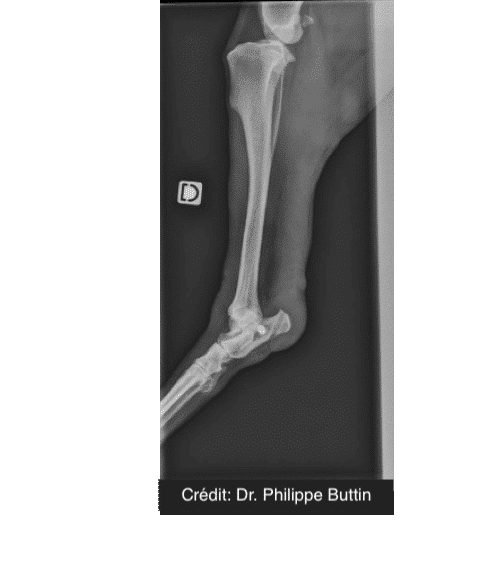

Reconstruction of tarsal medial collateral ligament

Radiologické snímky